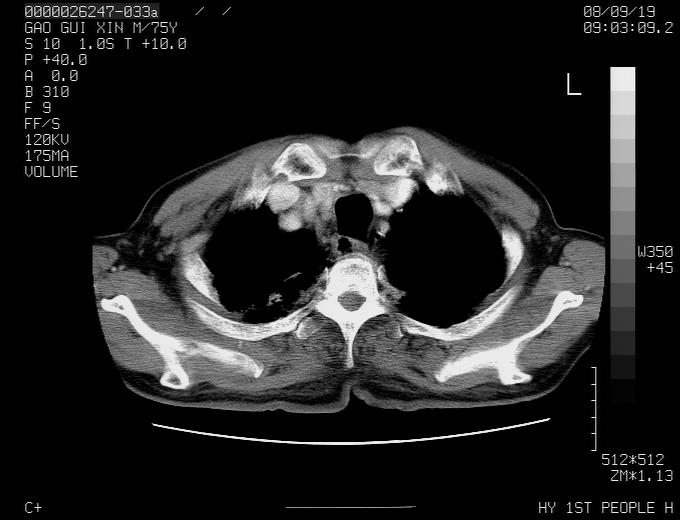

感谢各位老师的意见,左上肺病灶,我本人趋向结核,原因:左上肺见两个类圆形结节,仔细回顾4月份ct似乎原片在该处有条片状密度增高影,强化不明显。

现上传增强片,请各位老师仔细帮我看一下。

右上肺可见条索状影,并可见钙化,左上肺结节可以考虑为结核球,但气管前腔静脉后有肿大淋巴结,本人觉得左上肺结节不能排除转移瘤的可能,右上肺为陈旧性结核灶。

左肺上叶周围性肺癌并纵隔多组lnm.不可能是tb.

左肺上叶尖段瘢痕癌并纵隔淋巴结转移解释更好一些.